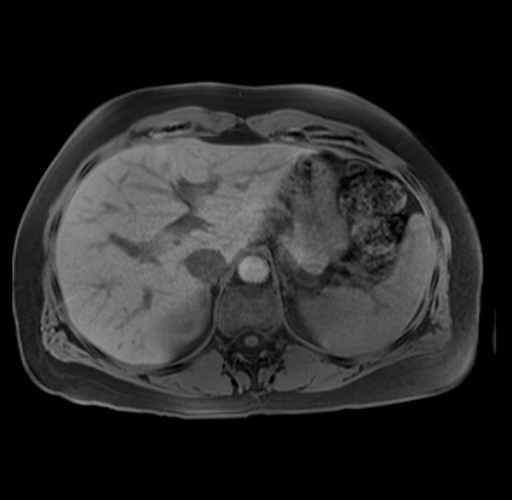

Laparoscopic distal pancreatectomy with possible splenectomy [case 14]

Imaging Analysis

Look through the patient's CT scan to identify any areas of concern for the necessary procedure.

Based on your CT findings, which issue(s) are present and would give reason for "planned slowing down moment(s)" in this case?

Considering a standard distal pancreatectomy procedure, what step(s) of the operation would you do differently in this case?